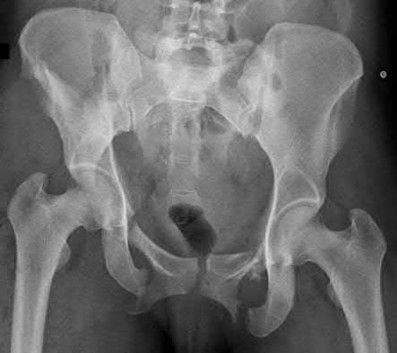

2. # A 35-year-old woman is involved in a head-on collision while driving. Initial radiographs are shown in Figures 8a and 8b. Injury to what vessel increases the risk for osteonecrosis of the injured bone?

5. Artery of the tarsal sinus Corrent answer: 4

The patient has a Hawkins type III talar neck fracture-dislocation with a risk of osteonecrosis ranging from 69% to 100%. Anatomic studies have shown that the artery of the tarsal canal supplies the lateral two thirds of the talar body.

The other vessels listed provide no significant contribution to the talus.